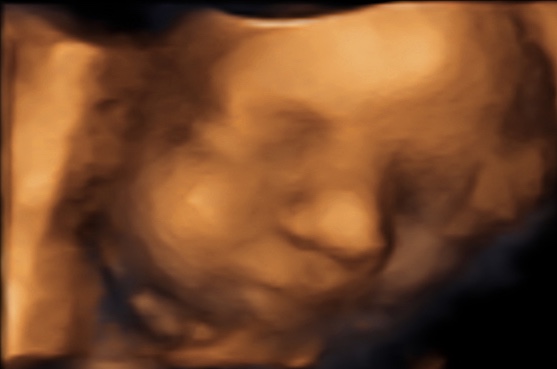

30 weken